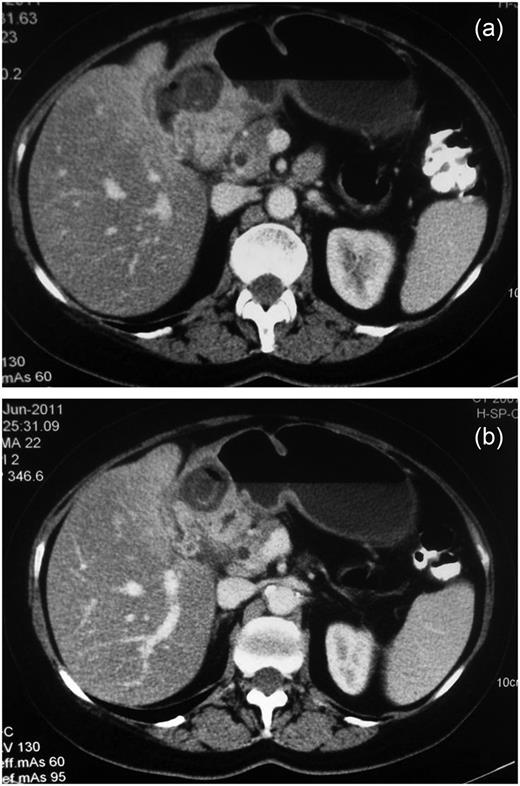

Radiological examinations performed included a chest/abdominal radiograph which were normal. The patient proceeded to have a computed tomography scan of the abdomen and pelvis with oral and intravenous contrast as shown in Fig. 1a and b. The CT scan shows a large gallstone as well as air within the gallbladder. The gallbladder is adherent to the distal gastric antrum and there is a slight deficiency of the wall of the gallbladder that appears to communicate with the antrum indicating a cholecystogastric fistula. There are some mild associated inflammatory changes around the gallbladder.